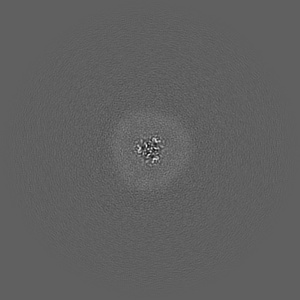

Cryo-EM structure of the human P2X7 receptor in the UB-MBX-46-bound inhibited state

Single-particle2.53 Å

A polycyclic scaffold identified by structure-based drug design effectively inhibits the human P2X7 receptor.